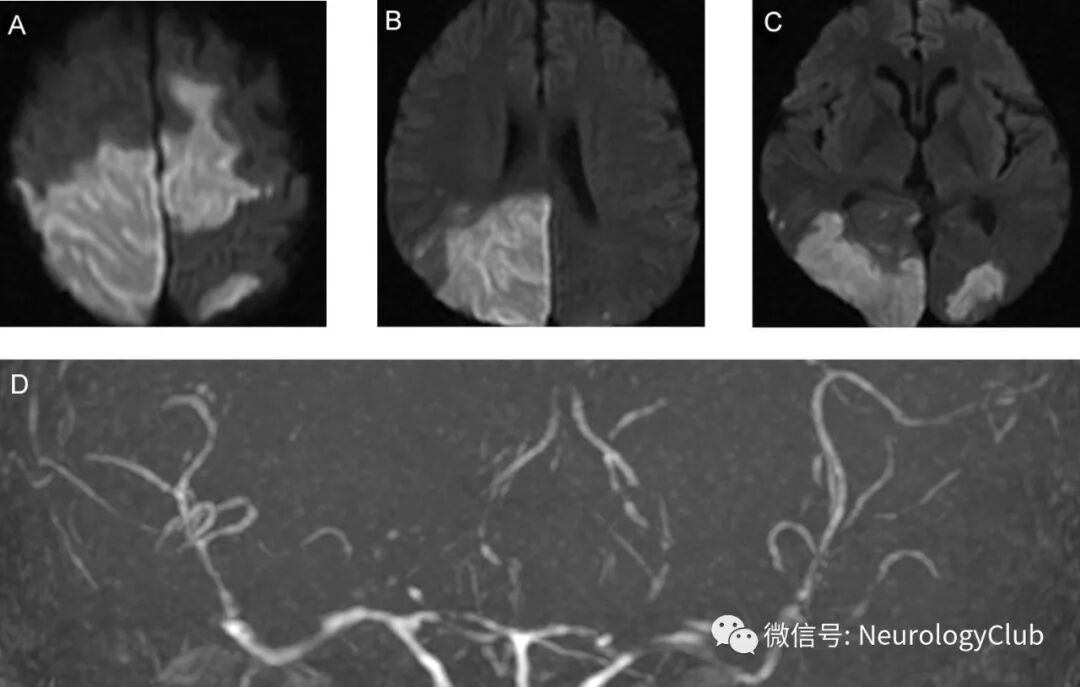

52岁男性,因扩张型心肌病所致终末期心功能衰竭行心脏移植。术后第8天,患者出现全面强直-阵挛发作。发作间期脑电图未见明显异常,实验室检查无殊。行头颅MRI和MRA检查。可见大脑半球后部多发T2高信号病灶。未见急性脑梗死或颅内血管异常(图1)。考虑为他克莫司治疗所致的PRES。为避免病情恶化,将他克莫司减量维持在正常血药浓度下限。此外,严格控制血压防止脑水肿加重。数小时后患者完全恢复。术后第18天,患者出现意识状态改变伴双侧肌力下降(2级)。影像学提示双侧额顶枕叶新发急性梗死以及多处脑血管弥漫狭窄(图2)。行DSA检查提示经典的脑动脉腊肠样外观,是RCVS的特征性改变(图3A)。实验室检查无血管炎相关证据。停用他克莫司,并给予尼莫地平治疗。患者血管痉挛较前改善(图3B)。左上肢肌力恢复至3级。随访3月,影像学未见新发梗死和血管收缩改变,但肢体肌力尚未完全恢复伴视敏度下降。

(图2:A-C:DWI可见双侧额顶枕叶新发急性梗死;D:MRA可见大脑前动脉,中动脉和后动脉弥漫狭窄)